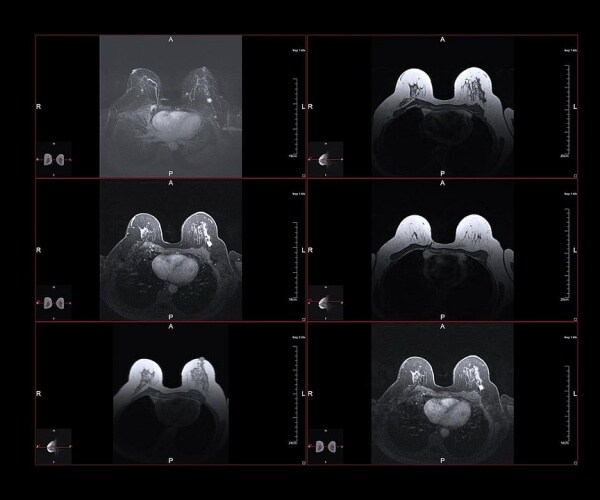

In the study, published March 9 in the European Heart Journal, scientists used artificial intelligence (AI) to examine more than 120,000 mammograms. The technology measured calcium deposits in arteries that run through breast tissue.

These calcium deposits, called breast artery calcification (BAC), can cause blood vessels to stiffen, a possible sign of heart failure.

Using AI, the team sorted artery deposits into four categories, ranging from none to severe.